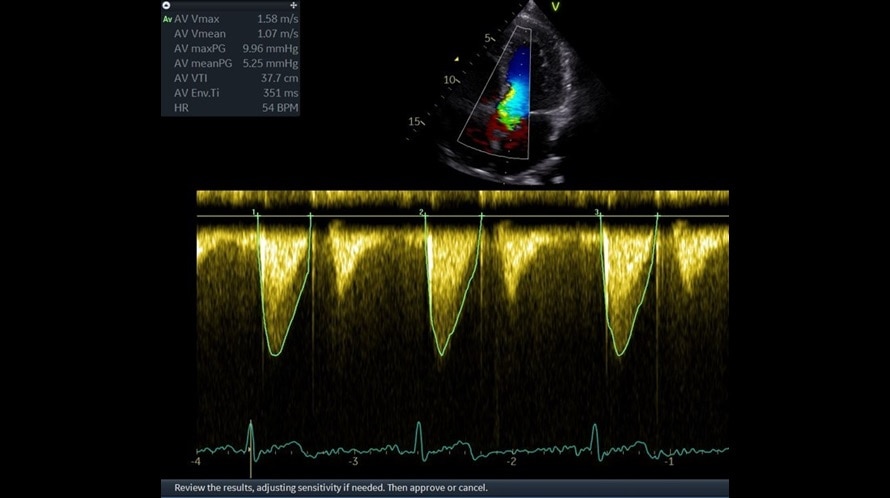

Режим цветового тканевого Доплера (TVI)

Отображает динамическую информацию от движущихся тканей сердца, позволяя с легкостью определять функцию левого желудочка.